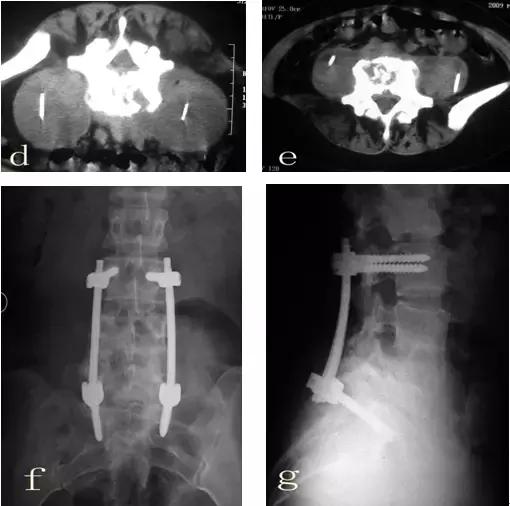

患者郭某,女性,25岁。因腰痛一年余,曾经在多家医院就诊,诊断为腰椎间盘突出,给予对症治疗,当时有所减轻,近来腰痛加重,经检查后考虑腰椎结核而到我院就诊。查体:脊柱向右侧弯曲,L4-5棘间压痛,叩击痛。左侧腹股沟区可触及100px×125px包块,触之波动感。实验室检查:血清抗结核阳性,血沉69mm/h,C-反应蛋白164.9mg/dl,PPD试验强阳性。腰椎平片(图a)示:腰4/5间隙变窄,L4椎体上缘骨质破坏。腰椎CT(图b)示:L4、L5椎体骨质有破坏,并有死骨形成,双侧腰大肌内可见液性暗区。腰椎MRI(图c)示:椎间盘等T1略短T2信号,临近骨组织呈长T1长T2信号,正常椎间盘信号消失,L4椎体下半部分L5上半部分骨质破坏,周围软组织肿胀,腰椎双侧腰大肌及骶前脓肿形成。入院诊断:腰椎结核(L4/5),腰大肌脓肿(双侧),骶前脓肿。入院后给予H.R.Z.E初治方案,同时在CT引导下行双侧腰大肌脓肿穿刺置管引流术(图d),引流后病人症状明显缓解,血沉(36mm/h)、C-反应蛋白(97.9mg/dl)明显下降,复查腰椎CT(图e)脓肿明显减少,经过抗结核治疗四周后给予行后路椎弓根钉棒系统内固定、前路病灶清除取髂骨植骨融合术(图f、g)。

该病例为腰椎结核的典型病例,具有腰椎结核的典型表现,包括血沉增快、C-反应蛋白升高、血清抗结核抗体阳性、PPD试验阳性、椎体破坏、死骨形成、腰大肌脓肿、椎旁脓肿、流注脓肿等,诊断明确。由于脓肿较大,结核中毒症状重,没有进行抗结核药物治疗,首先采用微创手术将脓液引流减少毒素吸收,进行规范抗结核药物治疗后再进行手术治疗。由于近几年脊柱外科的发展及相关的基础研究证实脊柱结核病灶内可以一期植入内固定材料,所以现在病灶清除植骨内固定术逐渐成为现代脊柱结核治疗的标准术式。

CT检查(图b、e)可见椎体破坏、死骨、椎旁脓肿、腰大肌脓肿及椎管内的变化等。

对于巨大的腰大肌脓肿并且张力比较大、结核中毒症状重、病人全身状况差的患者,虽然具有手术指征但是手术时机不成熟,可以先采用微创的手术方式进行穿刺将脓肿引流,这样可以迅速减轻病人的中毒症状,也可以减少脓肿流注的机会,也可以为下一步的病灶清除准备条件。

腰椎结核尤其在腰骶部的椎体破坏,前路内固定比较困难,可以选择后路内固定,前路经腹膜外病灶清除术,这样可以使病人早期下床,提高植骨融合率,缩短病人的康复时间。前路脊柱融合应当只融合已经破坏的节段(L4/5),待植骨块融合、结核治愈后取出内固定,可以尽可能多的恢复腰椎功能单位,可以减少临近腰椎间盘退变的几率。